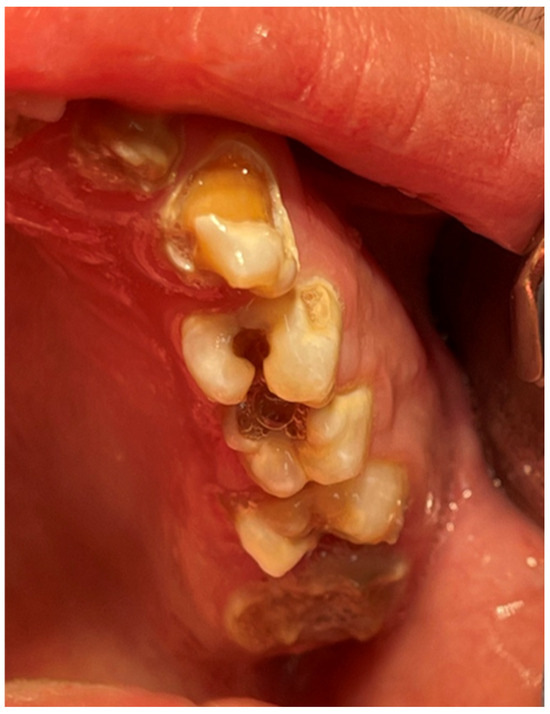

2. Case Report